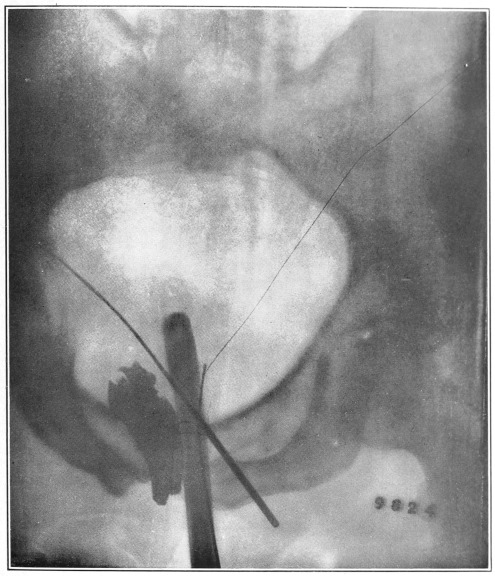

Nine Radiograph Illustrations Showing Mucus Channels and Cavities200

CHAPTER V.

Rebellion of our outraged Internal Economy.

The small intestine is that portion of the alimentary canal which begins at the stomach and ends at the large intestine. Its usual length is twenty feet. The diameter, which at the upper portion (duodenum) is two inches, gradually becomes less, until at the lower end it is but one inch.

Now, the length of the inner coat of this small intestine—the mucous membrane—is about double that of the intestine itself. Think of wearing a coat twice as long as yourself! How do you think this is accomplished in the case of the muscular tube under con­sid­er­ation? Well, Nature, having a most peculiar function to perform, has thrown this mucous coat or tube into a thousand folds (valvulæ conniventes, or “winking valves”). These folds form valves, occupying from one-third to one-half the circum­ference of the bowel. The greatest width of each fold is at the center, where it measures from a quarter to half an inch. Over this great expanse of mucous membrane we find studded ten million five hundred thousand intestinal villi, whose office it is to absorb the food substances in their passage through the canal.

Fig. 9.

Stomach, liver, small intestine, etc. (Flint.) 1, inferior surface of the liver; 2, round ligament of the liver; 3, gall-bladder; 4, superior surface of the right lobe of the liver; 5, diaphragm; 6, lower portion of the œsophagus; 7, stomach; 8, gastro-hepatic omentum; 9, spleen; 10, gastro-splenic omentum; 11, duodenum; 12, 12, small intestine; 13, cæcum; 14, appendix vermiformis; 15, 15, transverse colon; 16, sigmoid flexure of the colon; 17, urinary bladder.

Those that have observed the anatomical illustrations of the small intestines must have been struck by their apparently inextricably tangled convolutions. In life, these convolutions are constantly changing their locations, as though they were a mass of worms.

Fig. 10.

The cæcum, dorso-mesial view, showing the ileum-side of the ileo-cæcal valve, and the beginning of the three muscular ribbons. (Gerrish.)